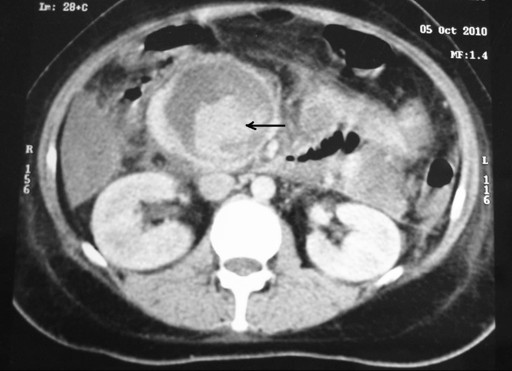

A 26-year-old female presented with a 2-month history of abdominal pain. She was admitted to our institution 7 days after the onset of the pain. She was diagnosed as having gallstone-induced severe acute pancreatitis with a large peripancreatic fluid collection. She was discharged on the 17th day after admission; a cholecystectomy and follow-up for the fluid collection were recommended. Three weeks after discharge, she developed sudden onset of severe abdominal pain with passage of black tarry stool. Hemodynamic stability was maintained. She was re-admitted to our institution. At admission, her pulse was 96 min-1 and her blood pressure was 100/70 mmHg. A lump was palpable in the epigastric region which was non-pulsatile. Hemoglobin was 7.8 g/dL (reference range: 11.5-15.5 g/dL). Upper gastrointestinal endoscopy showed blood in the stomach and duodenum with erosions in the body and antrum of the stomach. She was treated with proton pump inhibitors and blood transfusions. Four days after re-admission, she experienced one episode of hematemesis, and an upper gastrointestinal endoscopy showed blood trickling from the papilla; it was diagnosed as a case of hemosuccus pancreaticus. Contrast-enhanced computed tomography of the abdomen showed a large pseudocyst with extravasation of contrast within the cyst (Figures 2 and 3). The source of bleeding was not identified. Angiography identified a pseudoaneurysm of the gastroduodenal artery. Angioembolization failed due to technical reasons (partial embolization due to a rich collateral supply) and the patient had to undergo emergency surgery. We found that the pseudocyst was full of blood clots and there was a blister-like area in the wall of the cyst (Figure 4). After removal of the clots and slight pressure on the blister-like area, arterial bleeding was seen which was controlled with 4-0-polypropylene sutures. The pseudocyst was drained into the stomach. The patient had an uneventful postoperative course and was well at a 7-month follow-up.

Figure 2. CECT abdomen (axial) showing a large pseudocyst with extravasation of contrast within it (black arrow) (Case #2). |